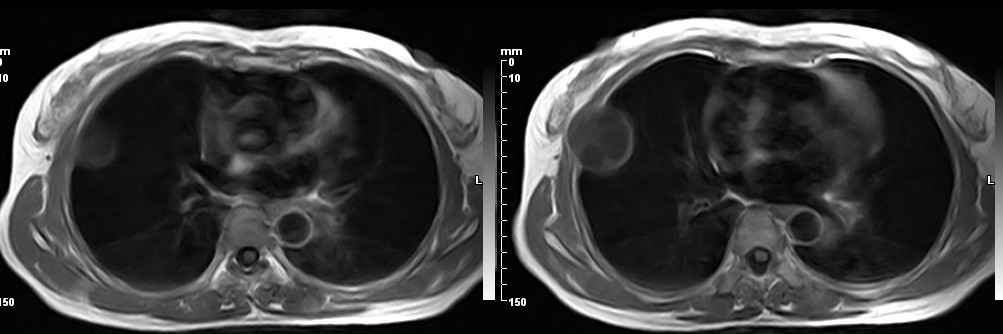

女,49岁。三年前因胸部不适在外院行CT检查诊断报告:右胸壁占位病变,考虑胸膜间皮瘤可能性大。现病人到我院检查了解情况。算是较典型的病变吧?大家看看MR比CT优点在哪里?

病检神经鞘瘤

液性信号符合神经鞘瘤囊变。